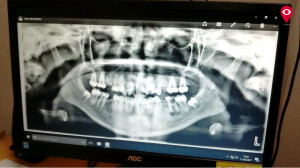

पॅनॉरॉमिक एक्स- रे मशिनचा वापर संपूर्ण तोंडाच्या रोगाच्या निदानासाठी केला जातो. या मशिनमुळे तोंडाचा जबडा, दात हे एकाच एक्स-रे मध्ये दिसते. ज्यामुळे तोंडाच्या आजाराविषयी निदान होतं.

पॅनॉरॉमिक एक्स रे मुळे डॉक्टरांना तोंडाच्या कुठल्याही भागातील आजारावर उपचार करणं सोपं होऊ शकेल. तोंडाच्या वरचा आणि खालच्या भागात असणाऱ्या आजारांचंही निदान अगदी अचूकपणे होण्यासाठी हे मशिन मदत करतं.

या मशिन्सचा फायदा विद्यार्थ्यांना शिकवण्यासाठी देखील केला जाणार आहे. यासोबतच रोगाचं अचूक निदान आणि उपचारांचं नियोजन करण्यासाठी या मशिन्सचा वापर केला जाईल. या मशिनमुळे तोंडाचा जबडा ही चांगल्या पद्धतीने दिसेल. त्यामुळे तोंडात असणारा त्रास आम्हाला कळू शकेल. डिजिटल ‘क्ष’-किरण या पद्धतीमध्ये रुग्णांना क्ष-किरणांची कमीत कमी बाधा होईल.